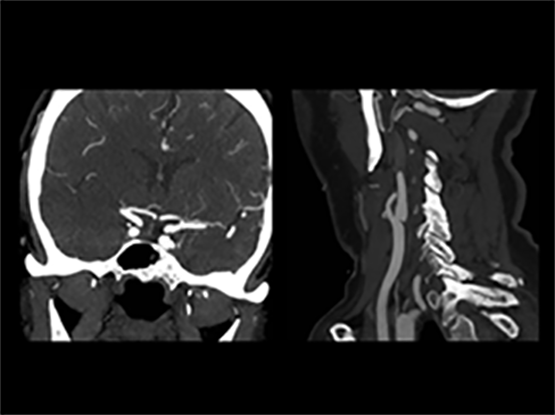

The clinical trial, known as ESCAPE (Endovascular treatment for Small Core and Anterior circulation Proximal occlusion with Emphasis on minimizing CT to recanalization times), shows there is a marked reduction in both disability and death among patients who receive ET for acute ischemic stroke. Ischemic stroke is caused by a sudden blockage of an artery to the brain that deprives the brain of critical nutrients, such as glucose and oxygen. Currently, the international standard of care based on Canadian, U.S. and European guidelines is to administer a drug called tPA when appropriate. Known as a ‘clot buster’, the drug dissolves the blood clot.

ET is performed by inserting a thin tube into the artery in the groin, through the body, and into the brain vessels to the clot. This is done under image-guided care using an X-ray. The clot is then removed by a retrievable stent and pulled out, restoring blood flow to the brain.

Endovascular treatments were first developed in the 1990s, but ET has only recently been technically possible. The ESCAPE team says the success of the trial can be credited to very fast treatment and the use of brain and blood vessel imaging. In ESCAPE, researchers were on average two hours faster in opening the blocked blood vessels than in previously reported trials.